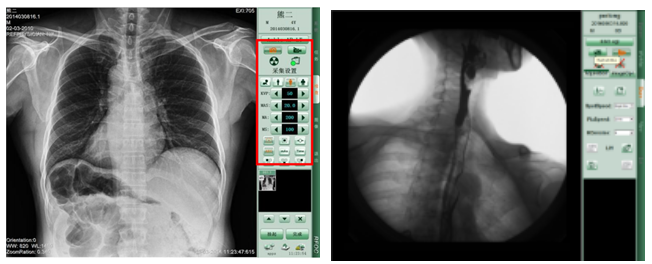

PLD7600平板動態(tài)DR拍片效果-普愛醫(yī)療